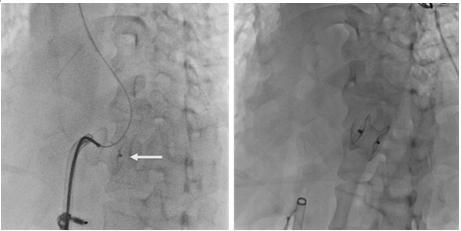

由于心肌梗死后心腔显著增大,导管无支撑点,正常导丝无法通过破口进入肺动脉,在张昌琳主任提议下,术中采用双导丝技术顺利将导管穿过破口,建立动静脉通路。在成功将输送系统到位之后,张端珍主任顺利将大小适合的封堵器置入破口处。术中患者无明显不适,未出现并发症,术后次日超声心动图检查示封堵器位置良好,仅有极少量残余分流。目前患者状态稳定,正准备进一步对冠状动脉行支架植入术治疗。

将封堵器植入破口处,左图为未释放状态(箭头所指为封堵器),右图为封堵器释放后形态。